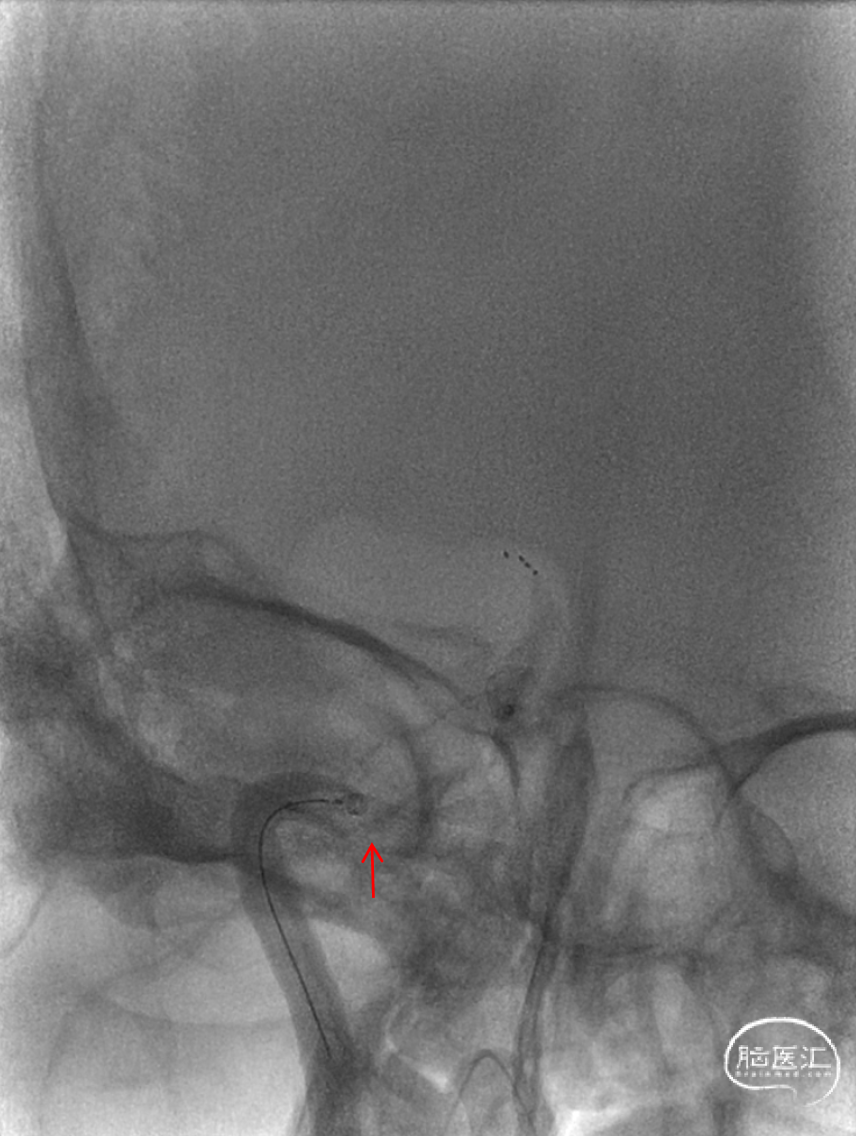

中间导管负压下抽吸受阻(蓝色箭头处)反复尝试无法通过。

遂Rebar-18微导管在Synchro微导丝引导下送至C6段(导丝前行受阻),冒烟证实ICA末端血栓(红色箭头)。

Rebar-18微导管送至RMCA M1段近端,冒烟证实为远端血管通畅(蓝色箭头)。

释放SAB 6-30支架,即刻造影见支架位置偏近,颈内末端血栓(蓝色箭头)。

在取栓支架锚定下,将中间导管通过岩骨段(红色箭头)并送至眼动脉近端(白色箭头),冒烟见颈内末端血栓。

Rebar-18微导管(白色箭头)原位回收支架,重新释放支架(红色箭头)。维持3分钟,支架锚定下将中间导管送至闭塞段近端,撤出微导管,打开三通继续前送中间导管至未见回流后连接负压抽吸(三通+2个50ml),抽拉结合回收支架。

颈内动脉末端仍闭塞(红色箭头),再次释放支架支RMCA M2段。维持3分钟后,回收支架,支架及抽吸装置内见数枚血栓,质韧。